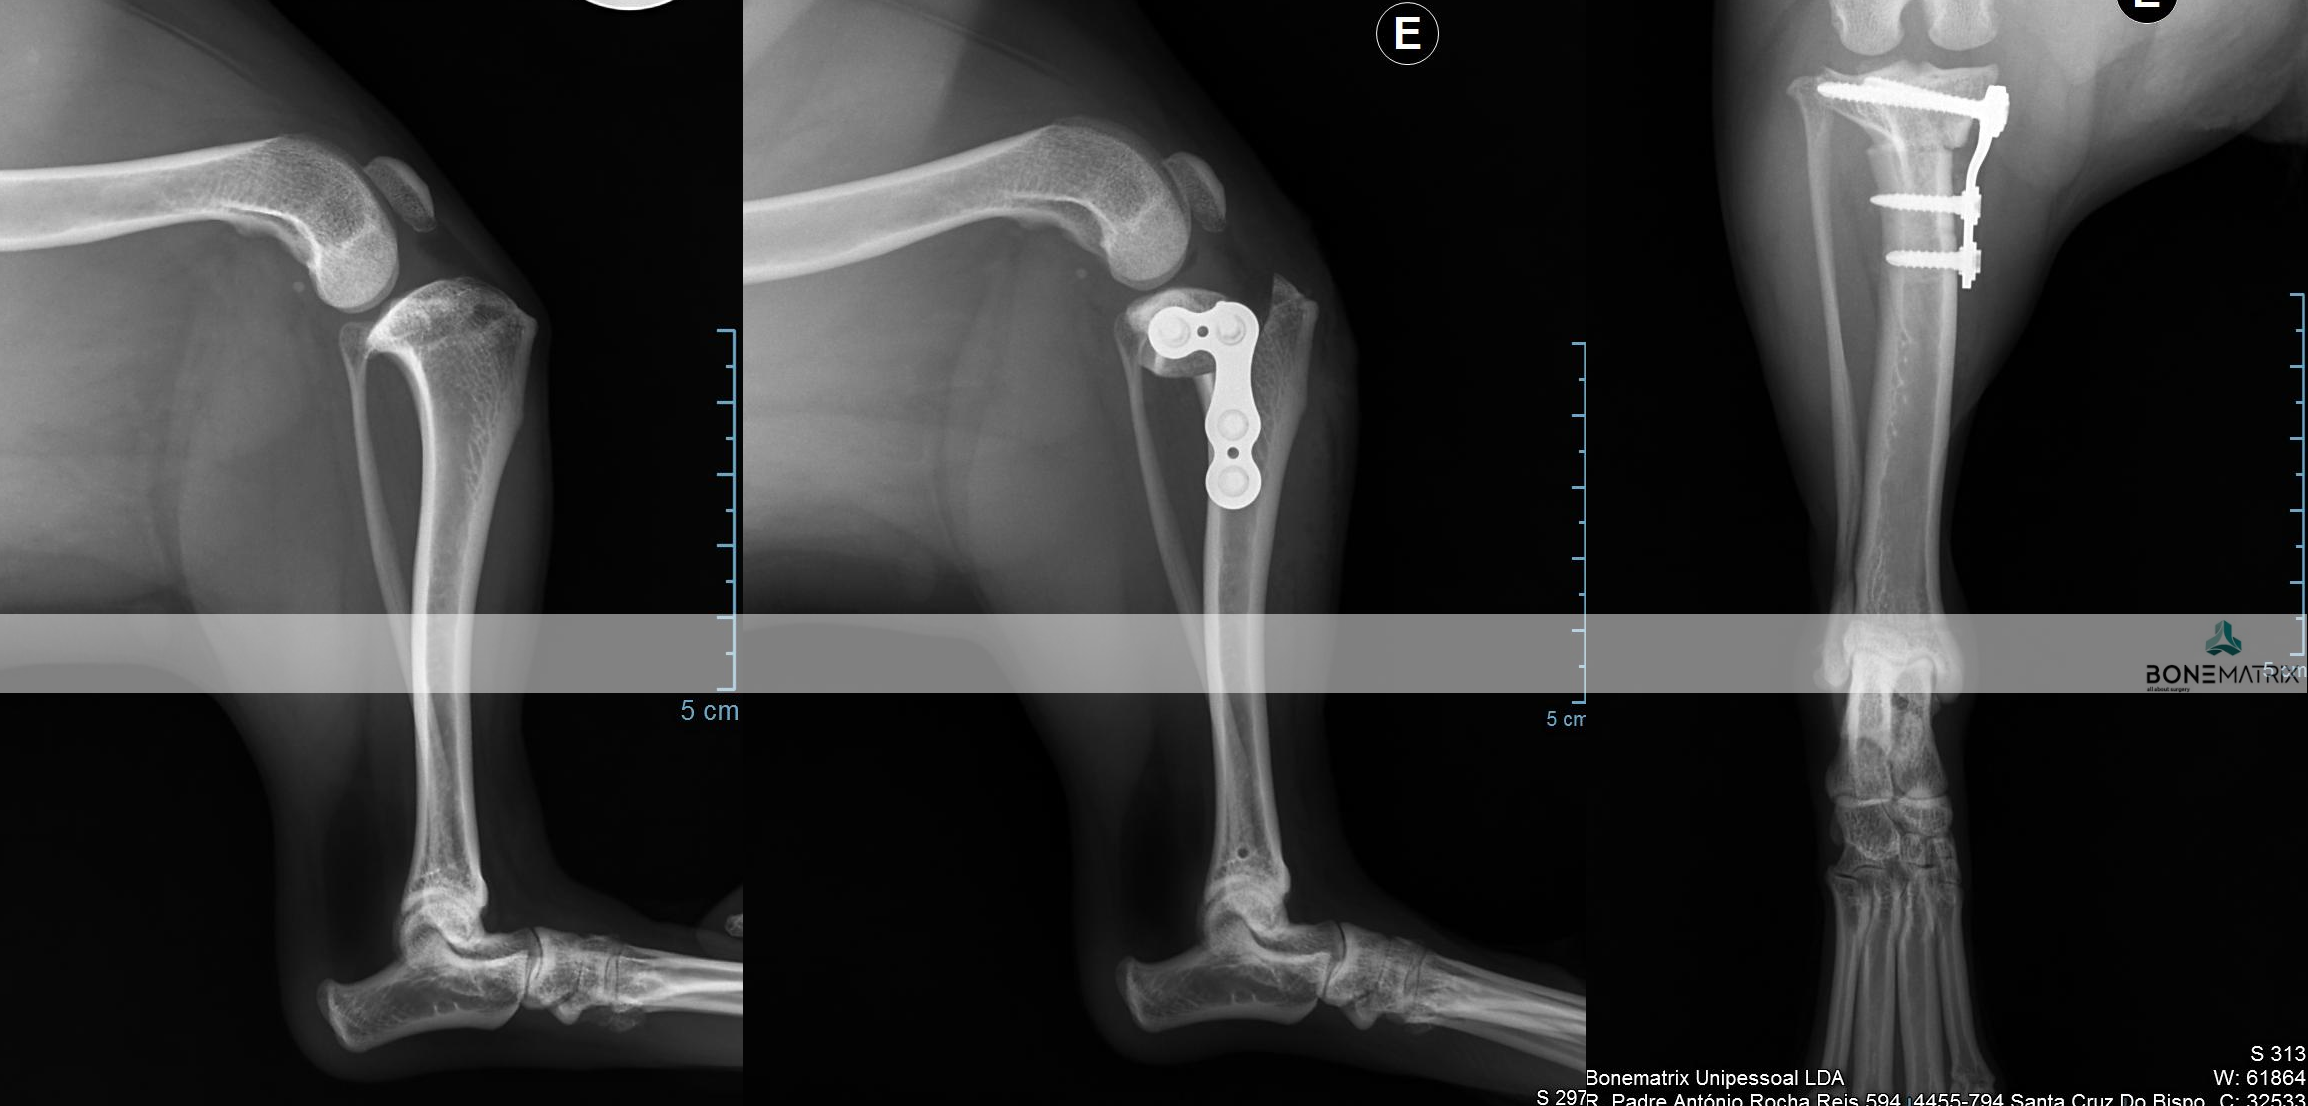

A TPLO é a técnica universalmente aceite na comunidade cientifica como sendo a opção terapêutica que garante melhores resultados no tratamento da rotura de ligamento cruzado cranial. Ainda assim, existem casos onde outras técnicas possam ser mais vantajosas pelo que o domínio de várias técnicas cirúrgicas representa uma vantagem determinante na seleção da melhor opção para tratar o seu animal.

A TPLO tem como objetivo alterar a forma como as cargas atravessam o joelho, para que se consiga um equilíbrio de forças que restaura a estabilidade articular. Desta forma não se tenta reparar o ligamento cruzado danificado, mas sim conseguir uma estabilidade dinâmica que torne desnecessária a existência de um ligamento cruzado íntegro.

Esta alteração acontece após um corte circular controlado no qual o fragmento criado é rodado e estabilizado na nova posição com recurso a implantes (placa e parafusos bloqueados).

DFO (distal femoral osteotomy) é um procedimento realizado como parte integrante ou abordagem única à patologia de luxação de patela (rótula).

A realização desta cirurgia implica a realização pré-cirúrgica de um planeamento cirúrgico baseado num estudo radiográfico.

No estudo realizado são feitas medições de vários ângulos relacionados com o alinhamento do membro posterior. Estes ângulos influenciam a direção sob a qual é exercida força sobre o joelho, podendo conduzir à luxação de patela.

Caso exista uma deformidade angular no fémur, é aconselhada a correção do ângulo em causa através da técnica DFO, para que a patela consiga permanecer alinhada na sua localização anatómica (sulco troclear).

A técnica consiste na realização de dois cortes no osso, para correção do defeito angular, e posterior estabilização dos cortes feitos com recurso a placas e parafusos bloqueados (implantes com um grau de segurança superior).

PTO (proximal tibial osteotomy) é um procedimento cirúrgico utilizado para correção de deformidades angulares presentes na tíbia.

A realização deste procedimento exige um estudo radiográfico com planeamento cirúrgico anterior ao procedimento cirúrgico. Neste são medidos ângulos relacionados com o alinhamento do membro posterior.

A cirurgia consiste na realização de dois cortes, previamente planeados, na tíbia, seguindo-se a sua estabilização por meio de placa e parafusos bloqueados (estes implantes apresentam um alto grau de segurança na sua utilização).

Dada a versatilidade desta técnica, várias patologias podem ser corrigidas com esta abordagem, nomeadamente luxações de patela e outras deformidades do membro posterior.